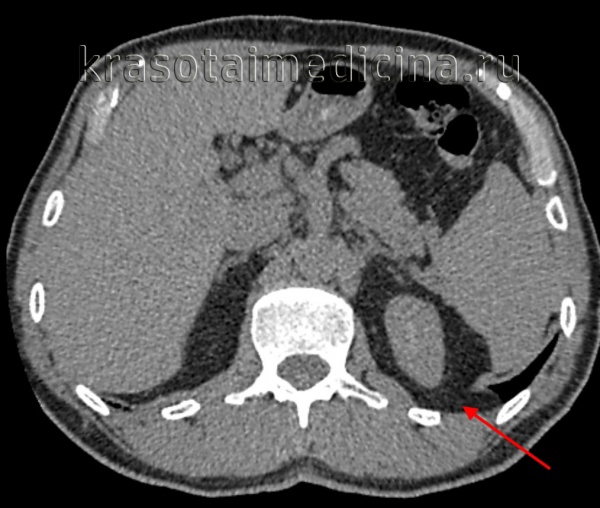

КТ ОБП. Диафрагмальная грыжа Бохдалека слева, связанная с истончением мышцы диафрагмы в задне-медиальных отделах с пролабированием забрюшинной клетчатки в краниальном направлении.